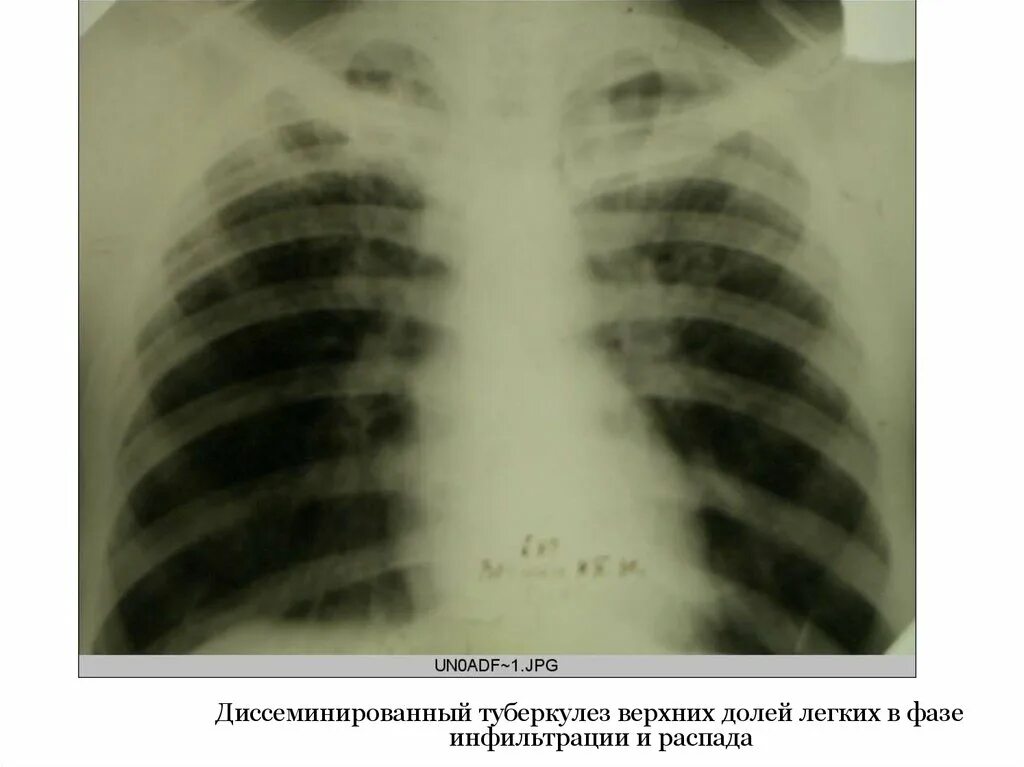

Диссеминированный туберкулез фаза инфильтрации